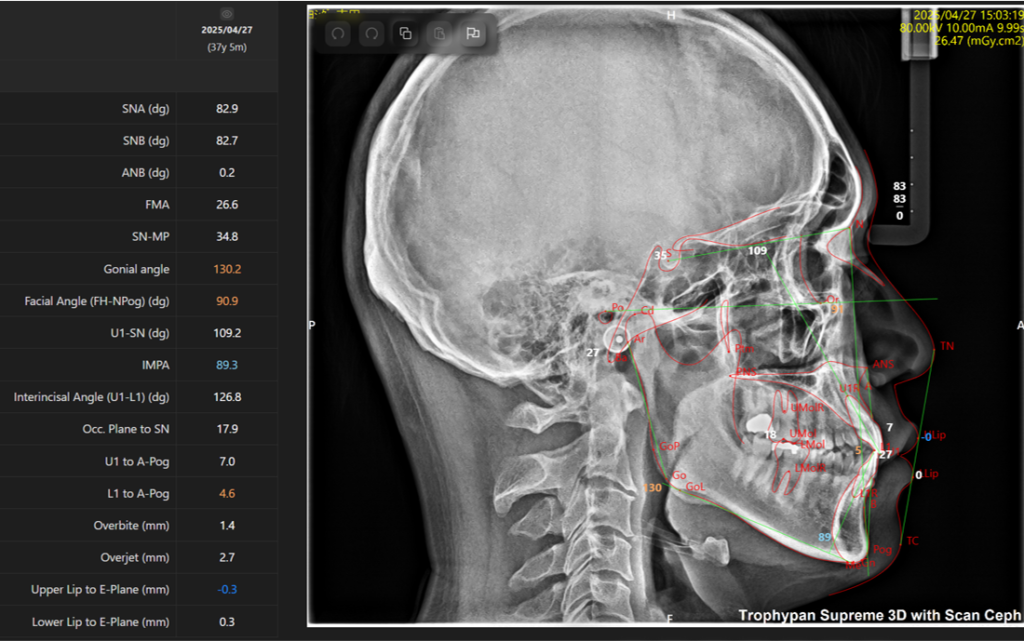

②セファロ写真

側貌写真では、頭部の位置に対する上下顎の前後関係(出っ歯や受け口など)や垂直関係(面長か丸顔かなど)を調べたり、歯の傾きや口元の突出度など様々な要因を数値化して正常値からどれくらい離れているかを確認します。

正貌写真では、正面から見た顔や顎の歪み、前歯の真ん中の位置などを確認します。

当院ではMoon Aligner Systemという診断ソフトを用いて、撮影後3~5分でレントゲン写真から以下の画像のようにAIが自動で分析値を即座に出してくれます。

この機能により、現時点の問題点や、治療方針について確信をもって説明することが可能になります。